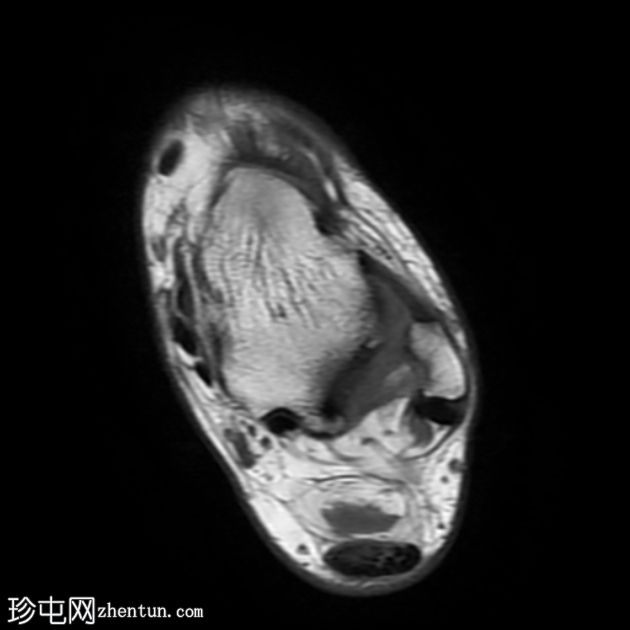

MRI

轴向

T1

跟腱插入

,伴有跟腱明显增厚,可诱发异常信号、跟腱后滑囊炎、跟骨后突及骨髓水肿信号。

Haglund综合征的检查结果令人印象深刻。

Haglund综合征是指以下三联征(Haglund三联征):

跟腱插入性病

跟腱后滑囊炎

Haglund畸形(即跟骨后上外生骨疣)